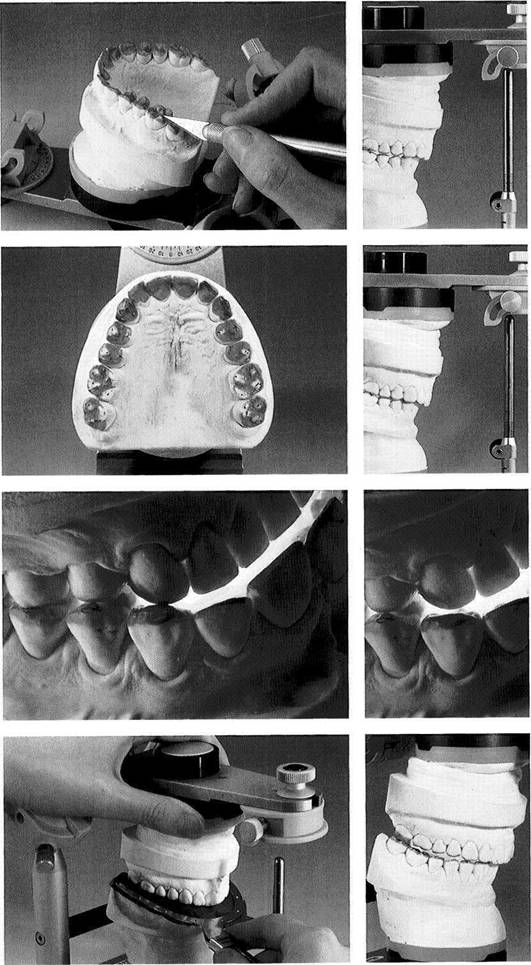

Occlusal Analysis Using Sectioned Casts

With the help of a sectioned mandibular cast with remov­able teeth mounted in centric it is possible to repeatedly experiment with alterations of the occlusion through selec­tive reduction of the teeth. With this method one can calcu­late, before cutting away any of the occlusal surfaces of the stone casts, approximately how much tooth structure would have to be removed to achieve the desired equilibration. A step-by-step analysis can be made on the mounted casts to determine how the planned corrections would affect the cuspal relationships and the vertical dimension. At this stage, then, it is possible to foresee whether the occlusion

can be stabilized through selective grinding alone or if prosthodontic or orthodontic measures will also be neces­sary. In some cases we also use occlusal analysis on sec­tioned casts as a tool for explaining the proposed treatment to the patient. The reasons for the planned occlusal reshap­ing of the natural teeth and the changes that can be expected must be thoroughly discussed with the patient.

Materials for occlusal

analysis with the help of a

segmented cast

Maxillary and mandibular casts are mounted in a relationship to the articulator corresponding to that of the natural teeth to the cranium and joints. The segmented mandibular cast with removable teeth has also been mounted in centric and thus is interchangeable with the solid mandibular cast. Strips of shim stock cut to the width of a premolar are used to test the occlusal con­tacts.

All of the posterior teeth and at least the lower canines should be removable as individual segments.

Centric occlusion

The segmented mandibular cast has been substituted for the solid mandibular cast.

The upper member of the articula­tor is closed to the first occlusal contact.

Preliminary inspection suggests that occlusal equilibration by selec­tive grinding could be accom­plished only with considerable loss of tooth structure in the molar region.

651 Lingual view of the teeth in centric occlusion

In this lingual view the functional open bite in the premolar and ante­rior region becomes especially ap­parent.